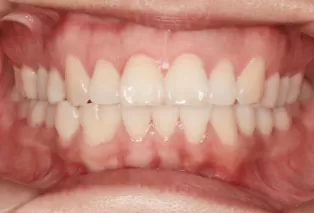

After Treatment

Intraoral photos after treatment